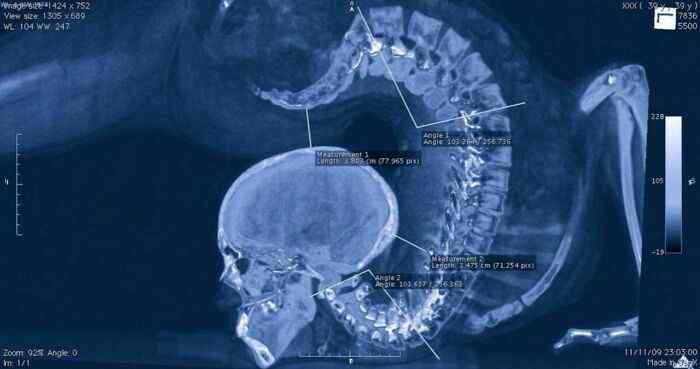

A Gymnast Performing An Exercise on X-Ray